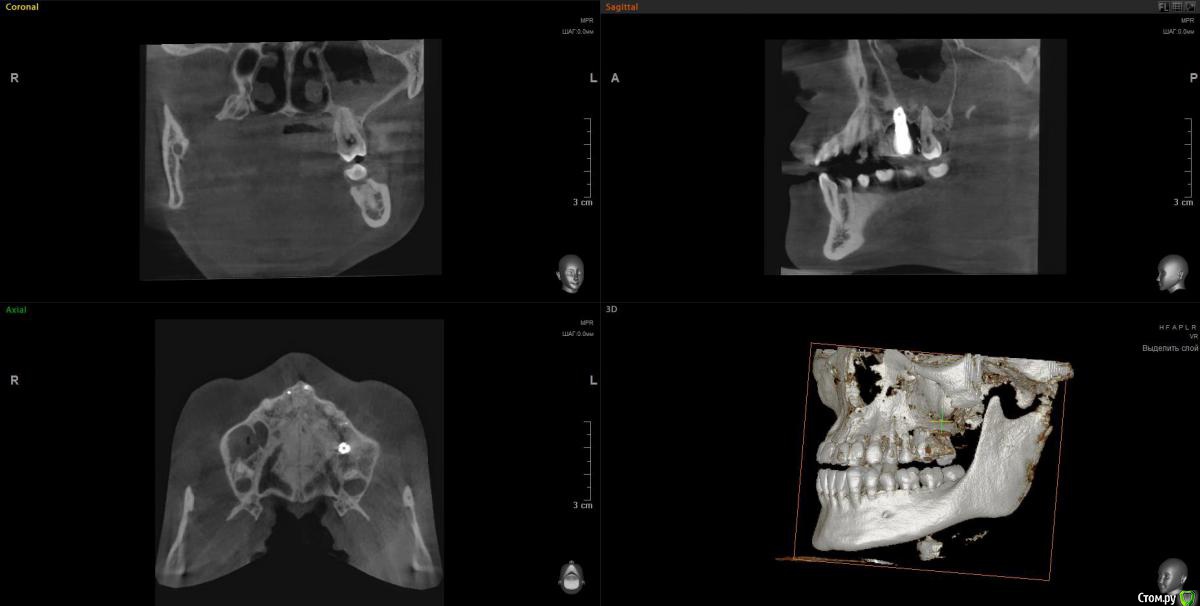

Lunar Опубликовано 8 апреля, 2020 Поделиться Опубликовано 8 апреля, 2020 Добрый день!Подскажите, пожалуйста, можно ли как-то разрулить ситуацию с левой стороной верхней челюсти..2014-2015гг - удаление 6 зуба, синуслифтинг, имплантация, протезирование. Все этапы отдельно. После синуслифтинга воспалилась пазуха и через n-ные промежутки времени делает это до сих пор и вот прямо сейчас в том числе (3 или 4ю неделю не могу с ней совладать). Ранее антибиотики решили вопрос с носовыми кровотечениями, но с остальной симптоматикой помогают лишь временно. Вместе с пазухой болит 7 зуб (из-за нее, или пазуха из-за зуба - один из вопросов..). Пару недель назад на десне над 7ой образовалось воспаление (гнойник). Сейчас десна поджила, зуб ноет тише, болит уже не половина головы, а только в районе пазухи, температура перестала повышаться. За 5 лет болеть все начинало от переохлаждения, само по себе и после стоматологических манипуляций в области импланта и 7 (раза 3 или 4 делали контакты, тк в промежутки все время все забивается).Тк прижало весьма не вовремя, почти все стоматологии закрыты, я буду очень благодарна, если сможете посмотреть снимки ( скрины кт после удаления, после синус лифтинга и недельной давности, только не уверена в правильности проекций..) и сориентировать по вопросам:1. Воспаление в пазухе связано ли с зубами?2. Депульпирование или удаление 7 зуба поможет снять воспаление? если это возможно определить по снимкам.. 3. Можно ли как-то исправить ситуацию в области импланта, в плане того, что заменить царь-коронку на что-то более компактное, чтобы оно начиналось не в складке, а поближе к остальным зубам? Удалять ли имеющийся?. Попробовать повторно нарастить кость и/или десну.. или только менять коронку, чтобы создать нормальный контакт между зубами, снять воспаление, и можно было бы полноценно пользоваться этой многострадальной стороной..С какой стороны мне вообще к этому всему подступиться или лучше не трогать?Заранее большое спасибо! Ссылка на комментарий

wladdX Опубликовано 9 апреля, 2020 Поделиться Опубликовано 9 апреля, 2020 Несколько скринов Ссылка на комментарий

Lunar Опубликовано 9 апреля, 2020 Автор Поделиться Опубликовано 9 апреля, 2020 Несколько скринов25_1.jpg25_2.jpgimp_1.jpgimp_2.jpg27_1.jpg27_2.jpgспасибо за скрины Ссылка на комментарий

Irouil Опубликовано 9 апреля, 2020 Поделиться Опубликовано 9 апреля, 2020 https://yadi.sk/d/FRKX9i80axqaUgПосмотрел я Ваше КТ. На мой взгляд, проблема чисто ЛОРовская, но... ЛОР врач может придраться к состоянию в полости рта и формально будет прав, поэтому Сначала проверить на витальность 7ку (вероятнее всего все же придётся депульпировать) Клинически осмотреть 5-ку (стоматологу терапевту). Потом к лору. Имплантат к пазухе вообще не имеет никакого отношения 1 Ссылка на комментарий